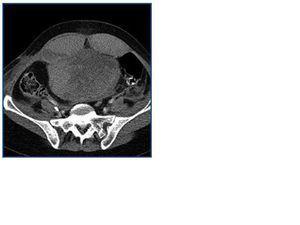

Tratada con metilprednisolona, ciclofosfamida y plasmaféresis (anticoagulación con citrato y reposición inicialmente con albúmina y posteriormente combinada con plasma) persiste deterioro de función renal con creatinina de 8,4 mg/dl y oliguria iniciándose hemodiálisis sin heparina. A los 13 días presenta dolor en higastrio y fosa iliaca izquierda tras un episodio de tos. Aparece una masa abdominal y anemización de 4 puntos. El TAC abdominal objetiva un hematoma de la vaina del recto anterior izquierdo (Figura 1). Se trasfunden 3 concentrados . El estudio de coagulación incluyendo factores es normal excepto Yvy de 10 minutos. Tres días después nuevo dolor en fosa iliaca derecha, con íleo paralítico y anemización de 3 puntos. El TAC objetiva un hematoma en ambos músculos rectos anteriores que se extiende hacia el espacio de Retzius y pelvis (Figura 2). Precisa 4 concentrados de hematíes. Se consulta con el servicio de cirugía y radiología intervencionista decidiendo tratamiento conservador expectante y asociar antibióticos (amoxicilina clavulánico) así como nutrición parental.

Figura 2.